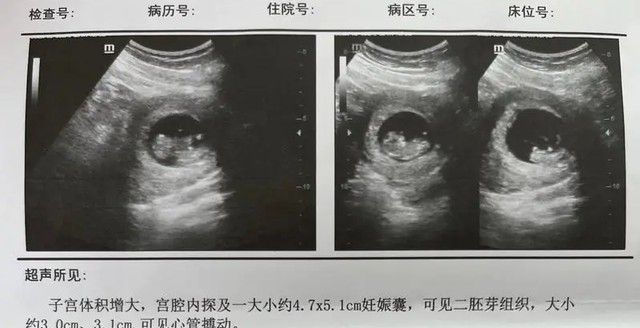

原来女子在刚刚怀孕的时候,去医院检查的时候看到是双胞胎,心中的即喜悦又恐慌,因为她还没有结婚,属于未婚先孕,但是肚子是两个小生命,她又舍不得。

原来这两天,又发生了很多事,女子去医院检查,说如果是引产的话风险很大,说不定还要二次手术进行剖腹产,毕竟胎儿大了,风险这么高的手术将来很有可能就不能再当妈妈了,最严重甚至还会一尸三命。

但话说回来,孩子已经33周,毕竟是两个小生命,作为肚子里孩子的妈妈,她是最心痛的!